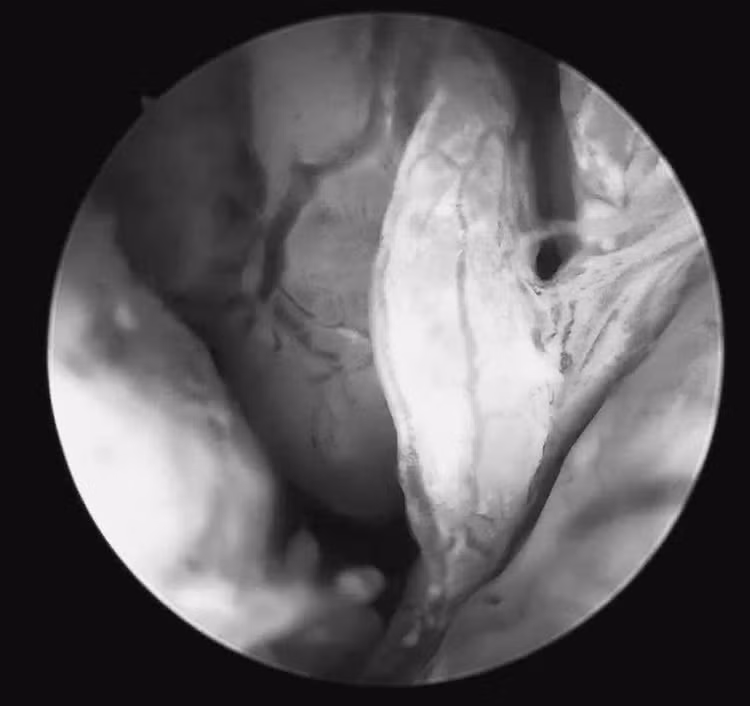

ngang-vang-3.jpg

Hình ảnh tổn thương qua nội soi - Ảnh BVCC

Quá trình soi diễn ra an toàn, nhẹ nhàng. Bệnh nhân hoàn toàn tỉnh táo và có thể quan sát trực tiếp hình ảnh buồng tử cung trên màn hình: niêm mạc nham nhở, tăng sinh không đồng đều, nhiều mạch máu bất thường, những dấu hiệu gợi ý tổn thương ác tính. Mẫu sinh thiết được lấy ngay trong quá trình soi để làm xét nghiệm mô bệnh học.